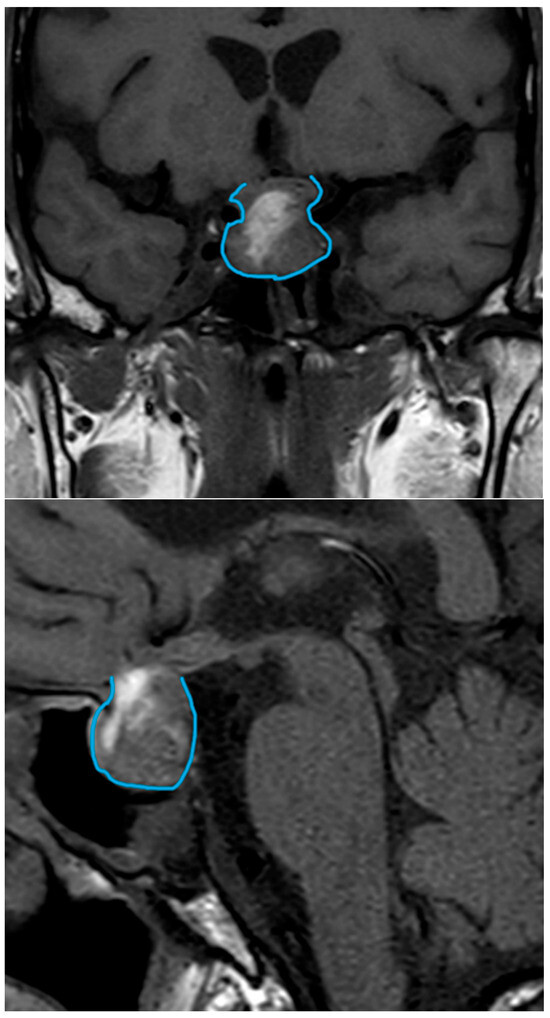

| Date | July 2018 | January 2019 | July 2019 | June 2020 | October 2020 | December 2020 | June 2021 |

|---|---|---|---|---|---|---|---|

| Prolactin (ng/mL) | 22.1 | 27.6 | 71.2 | 681.9 | 0.4 | 1.8 | |

| MRI | Macroadenoma (20 × 20 × 18 mm) with signs of pituitary apoplexy. Invasion of the optic chiasm, hypothalamus, and the left cavernous sinus. | 5 × 2 mm nodular structure that could be related to remnant glandular tissue. Persistent left deviation of the pituitary stalk. | Tumor growth (16 × 14 × 11 mm). Significant compression of the optic nerve and the optic chiasm. | Discrete decrease in volume of the tumor (13 × 12 × 8 mm). No compression of the optic nerve and the chiasm. | Volume reduction (13 × 10 × 6 mm). The structure is no longer in contact with the gyrus rectus and the subcallosal area. | ||

| Treatment | First surgical procedure | Second surgical procedure | Cabergoline started |